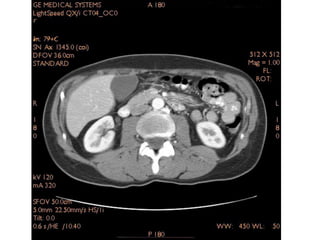

TC Helicoidal do Abdome

Fases de exame:

• Fase sem contraste EV

• Fase arterial: 20 – 40 seg.

• Fase portal: 60 – 120 seg.

• Fase de equilíbrio: 120 – 360 seg.